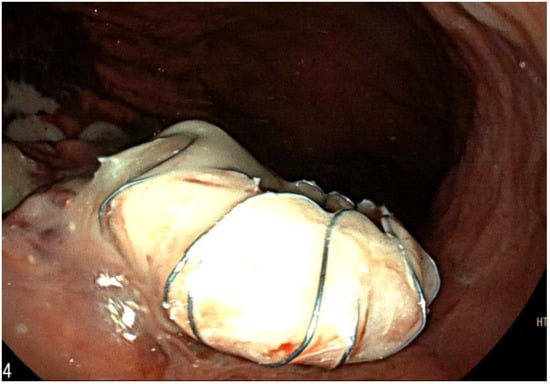

Figure 4.

EUS-guided trans-gastric drainage of the fluid collection using a 16 × 20 mm lumen-apposing metal stent (LAMS, Hot-Spaxus, Taewoong Medical Co, Gimpo, Korea).

Approximately two months after the hospitalization, they returned to the hospital with epigastric pain and fever (38 °C). Laboratory results showed a WBC count of 14,530/mm3 (neutrophils: 78%) and a CRP level of 163 mg/L (<5 mg/L), procalcitonin 0.14 ng/mL. Pancreatic enzymes and liver function test results were within the normal ranges. An abdominal CT scan showed the presence of multiple confluent fluid collections extending from the head to the tail along the entire pancreatic profile containing air (Figure 1). An endoscopic investigation and an endoscopic ultrasound (EUS) were performed. The upper endoscopy revealed the presence of a fistula opening of about 8 mm in diameter in the duodenum bulb with leakage of purulent material (Figure 2). EUS showed the presence of air in the fistula and a complex 5 cm fluid collection in the tail of the pancreas (Figure 3). An abdominal CT scan with gastrografin confirmed the fistulous channel originating from the first duodenal portion, which gives rise to two branches, anteriorly in the head of the pancreas and posteriorly in the tail. After a collegial reunion with clinicians, surgeons, radiologists, and gastroenterologists, it was decided to proceed with the drainage of the larger pancreatic collection in an attempt to heal the fistula with the duodenum. EUS-guided trans gastric drainage of the fluid collection was performed using a 16 × 20 mm lumen-apposing metal stent (LAMS, Hot-Spaxus, Taewoong Medical Co., Gimpo, Korea), obtaining drainage of copious purulent material in the stomach (Figure 4).